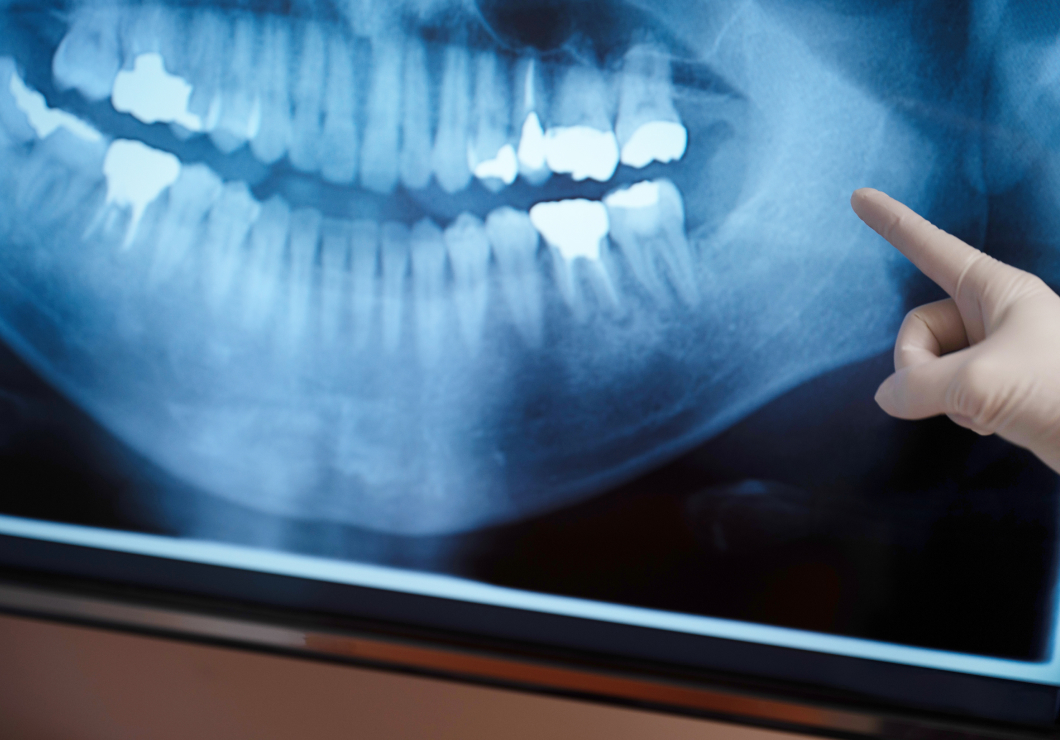

当院では、すべての患者さまに対してしっかりと、わかりやすく説明することを大切にしています。診療の前には、イラストや写真入りの資料を使い、「なぜこの治療やケアが必要なのか」「どんな方法があるのか」を丁寧にお伝えします。

患者さまお一人お一人の理解やご希望に寄り添い、ご納得いただいた上で治療を進めることが、満足度の高い治療につながると考えています。気兼ねなく、何でもご質問、ご相談ください。